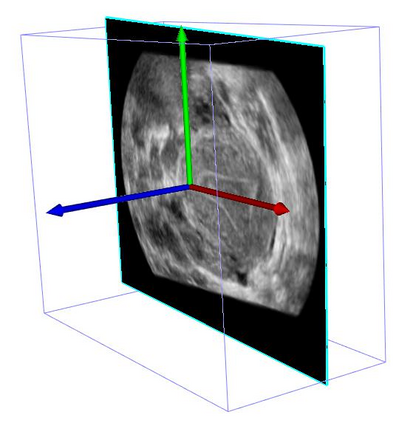

Standard plane (SP) localization is essential in routine clinical ultrasound (US) diagnosis. Compared to 2D US, 3D US can acquire multiple view planes in one scan and provide complete anatomy with the addition of coronal plane. However, manually navigating SPs in 3D US is laborious and biased due to the orientation variability and huge search space. In this study, we introduce a novel reinforcement learning (RL) framework for automatic SP localization in 3D US. Our contribution is three-fold. First, we formulate SP localization in 3D US as a tangent-point-based problem in RL to restructure the action space and significantly reduce the search space. Second, we design an auxiliary task learning strategy to enhance the model's ability to recognize subtle differences crossing Non-SPs and SPs in plane search. Finally, we propose a spatial-anatomical reward to effectively guide learning trajectories by exploiting spatial and anatomical information simultaneously. We explore the efficacy of our approach on localizing four SPs on uterus and fetal brain datasets. The experiments indicate that our approach achieves a high localization accuracy as well as robust performance.